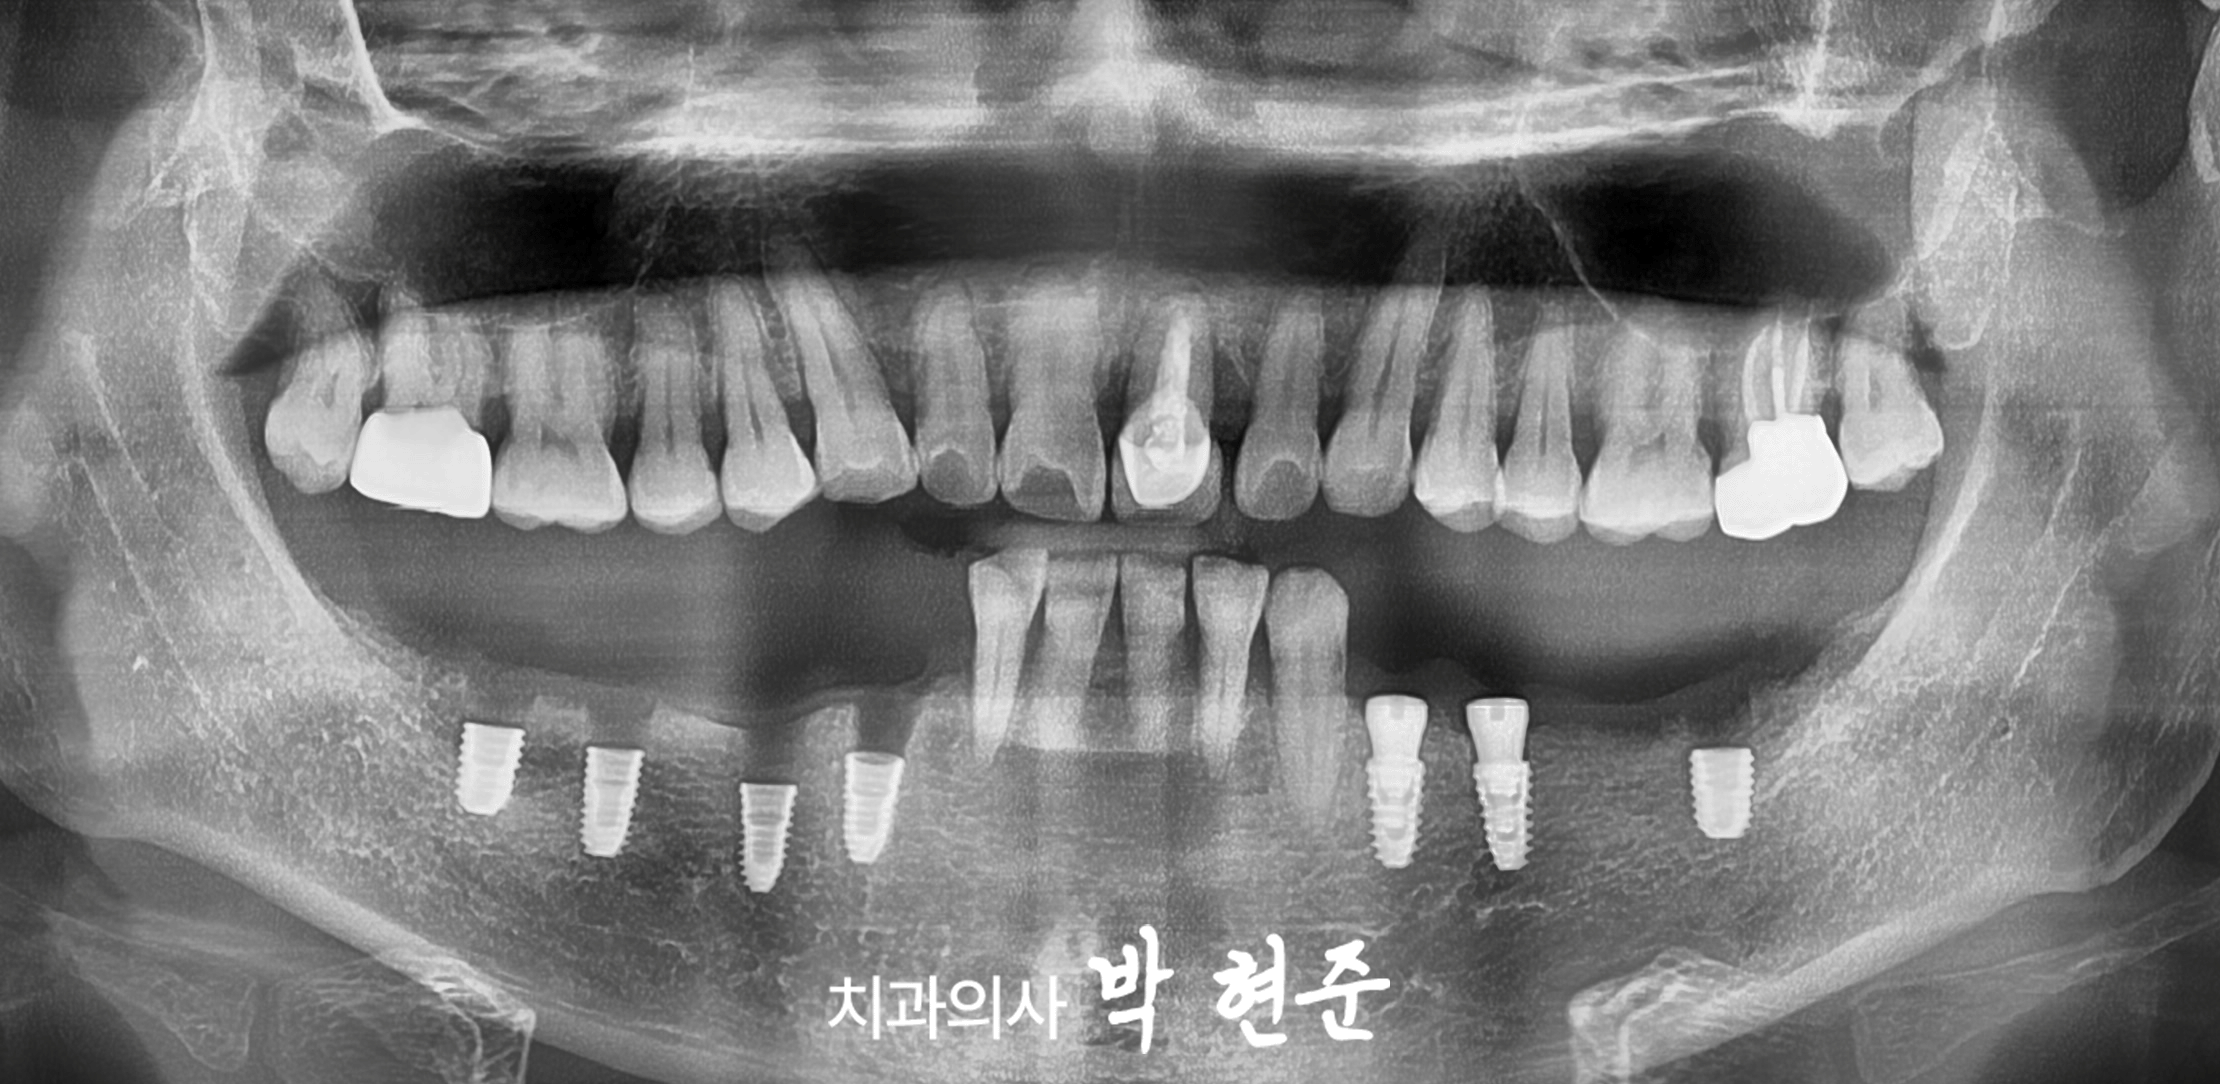

엑스레이 예시 사진을 관찰해보니

치관의 많은 양이 부러진 것으로 보여집니다.

이미 과거에 근관치료도 받았던 곳으로 보이기에

발치가 필요하겠습니다.

사진 상으로는 비어있는 구치부의

치조골 높이가 양호한 것으로 보이기 때문에

태평역임플란트 식립이 가능할 것으로 보여집니다.

파절된 이는 뽑고